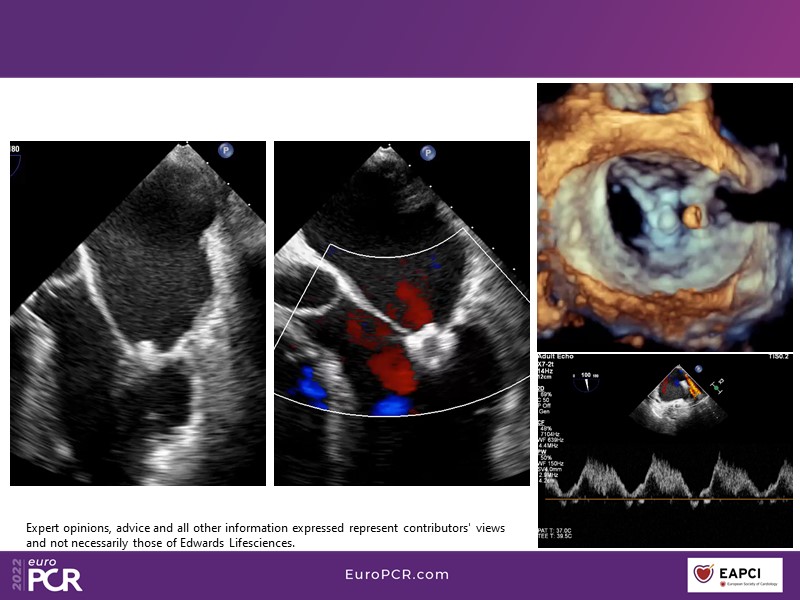

With study outcomes and clinical cases, this EuroPCR 2022 session will enable you to discuss the anatomical considerations that define suitable candidates for treatment of mitral regurgitation with the PASCAL platform and highlight key differentiators and tips and tricks for its use.

- To discuss which anatomical considerations define suitable candidates for the treatment of mitral regurgitation with the PASCAL platform

- To attend case-based discussions that will highlight key differentiators and tips and tricks when using the PASCAL platform to treat mitral regurgitation

- To participate in a recorded case demonstration using the PASCAL platform for the treatment of mitral regurgitation